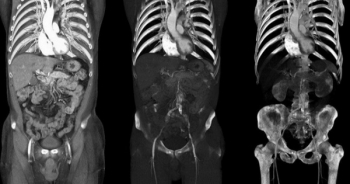

Một bác sỹ phẫu thuật tại một bệnh viện ở Massachusetts (Mỹ) đã cắt bỏ nhầm một quả thận của một bệnh nhân trùng tên với bệnh nhân có khối u.